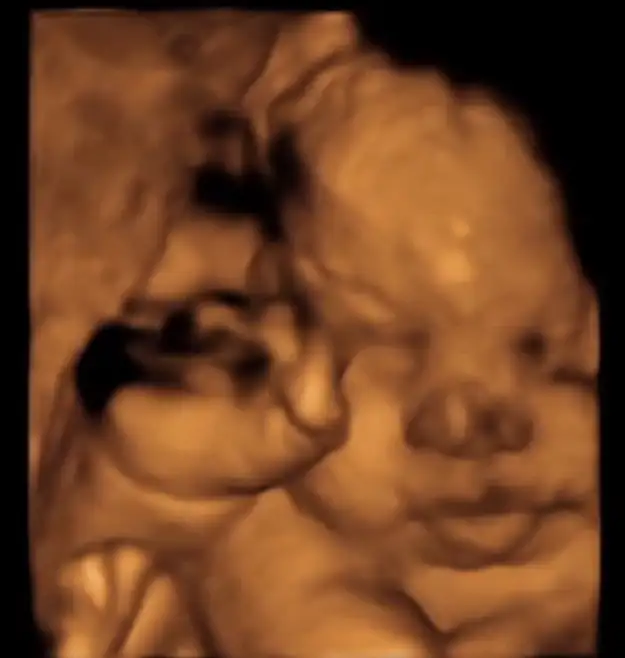

Ben her kontrole eşimle gidiyorum normalde , ama dünki mecburi hafta içi olunca eşim izin alıp gelemedi , ben tek gittim . Eşimle gittiğim her kontrolde iki elini, hatta ayaklarını bile yüzüne kapayan kızım , dün bana şov yaptı resmen . 2-3 tane güzel poz alınca pat diye sırtını döndü direkt , bu sana yeter dedi zaar